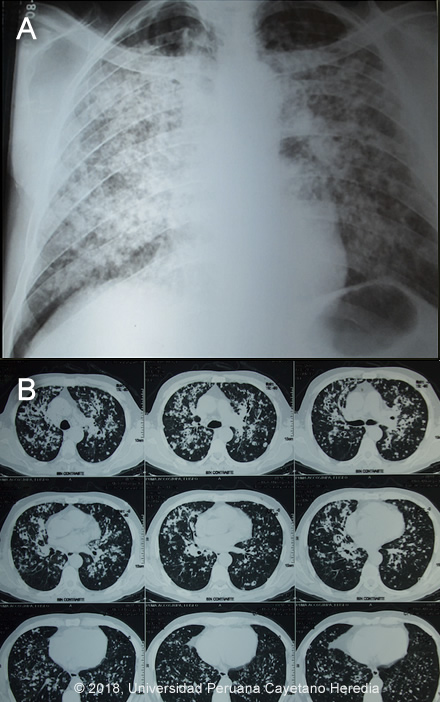

Epidemiology: Born in Cusco, but has resided the past 45 years in Tambopata, Madre de Dios, in the jungle as a farmer. Wife died 10 years ago of pulmonary tuberculosis and his son was successfully treated for gastrointestinal tuberculosis at the same time. The patient did not receive isoniazid preventive treatment. PMH: Treated 20 years earlier with an incomplete course of antimony for a chest ulcer which showed leishmania on a scraping. No recurrent skin ulcers. Physical Examination: BP: 85/60 mmHg, HR: 98x’; RR: 37x’; T°:36°C, Sat02: 85% at FiO2 21%. On examination, the patient appears chronically ill with wasting and respiratory distress. Oral Exam: friable ulcer with well-defined edges on the hard palate. Chest: Respiratory sounds audible with crackles and rhonchi bilaterally. Skin: Pallor of skin and mucous membranes. Abdomen: no visceromegaly. Neurologic examination: normal. Laboratory Examination and Imaging: Hematocrit: 41%. Hemoglobin:14.8 g/dl. WBC: 6.1 (0% bands, 65% segmented neutrophils, 3% eosinophils). Platelets: 397 000. Creatinine: 0.8mg/dl. Urea:36 mg/dl. Glucose: 87 mg/dl. Alkaline phosphatase: 119. AST/ALT: 27/37, Albumin: 4.5. Blood Culture x 2: Negative. Stool negative for ova and parasite including Strongyloides stercoralis. Chest X-ray: bilateral nodular and alveolar infiltrates (Image A). Chest CT-Scan: bilateral nodular lesions, some with cavitation, reticulo-nodular infiltrates and bilateral alveolar infiltrates (Image B).